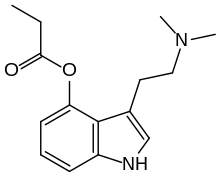

| 4-PrO-DMT | artificial | 4-OCOCH2CH3 | CH3 | CH3 | 4-propionyloxy-N,N-dimethyltryptamine | 1373882-11-1 |